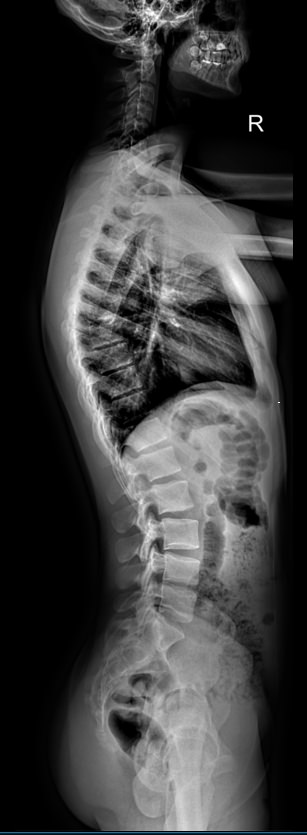

Изменения позвоночника хорошо видны на рентгене, который и назначают в качестве первичного обследования. Если симптомы говорят о поражении нескольких отделов позвоночника, а также когда необходимо выявить изменения на всей его длине, назначают стичинг. Это полный снимок всего позвоночного столба, состоящий из нескольких обычных прицельных снимков. Они «сшиты», то есть собраны цифровым способом ― на экране компьютера.

Что может показать стичинг позвоночника в боковой проекции

• Изменение физиологических лордозов и кифозов ― усиление или сглаживание;

• Деформация дуги в виде «ступеньки» ― выдвинутого позвонка,

• Изменения толщины межпозвонковых дисков;

• Склероз замыкательных пластинок  и костные разрастания тел позвонков;

• Остеопороз костной ткани позвонков;

• Переломы, вывихи, подвывихи;

• Новообразования.

Выполняется 3 снимка: шейного, грудного и пояснично-крестцового отделов, в боковой проекции. Каждый раз занять правильное положение помогает рентгенолаборант. Экспозиция одного снимка ― около 2 секунд, в это время необходимо задержать дыхание и не шевелиться.